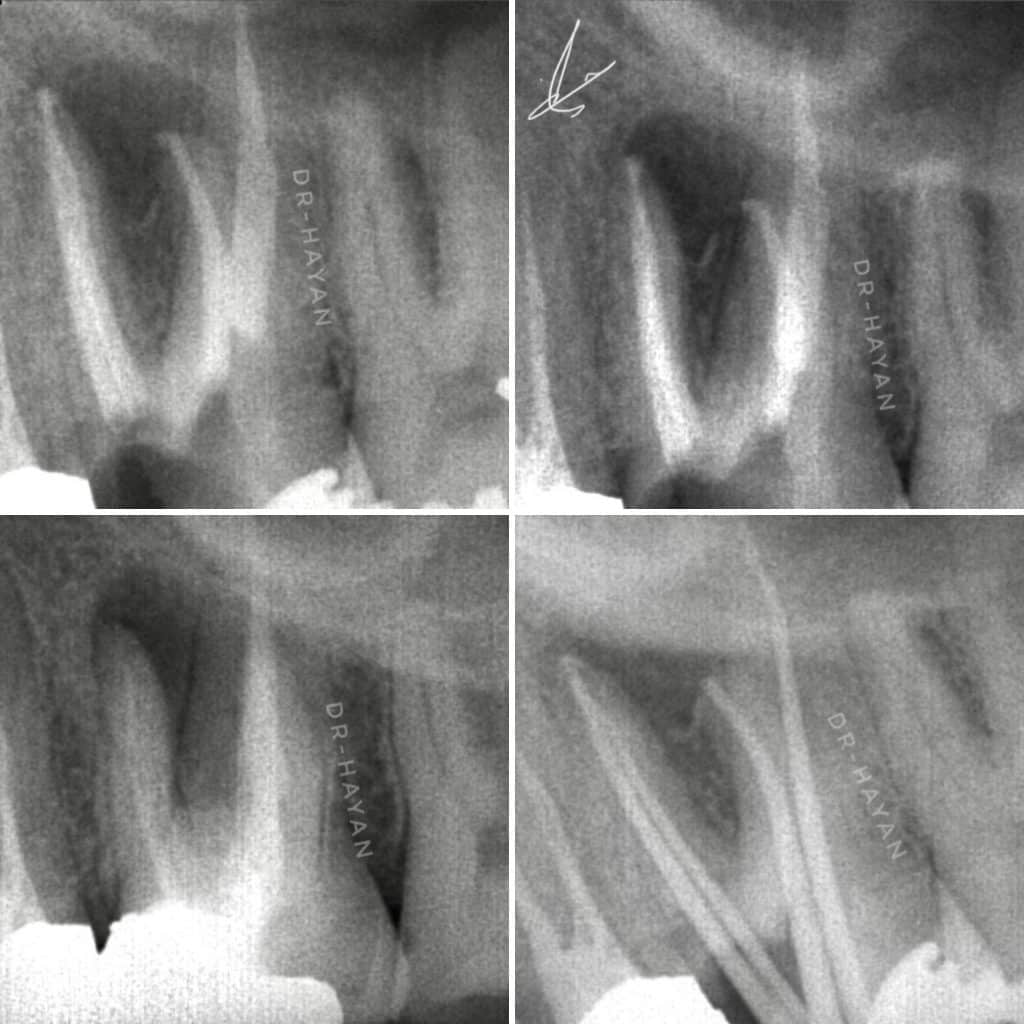

After 12 visit of irrigation protocol and intra canal medication

After completing drying the canal

Irrigation protocol for final obturation

WVC obturation by bio ceramic sealer